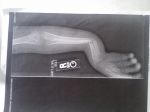

Max's 1st and 2nd injuries = all in 6 months time!

break #2.jpgbreak # 1.jpglittle boy.jpg

Yikes! Max has got me beat!